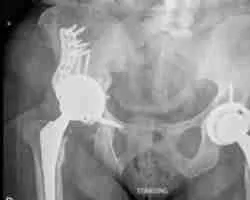

Dr. Morton is a hip and knee specialist who provides clinical and surgical services. His focuses are on joint replacements, complex reconstruction, robotic-assisted surgery, sports surgeries, and trauma care.